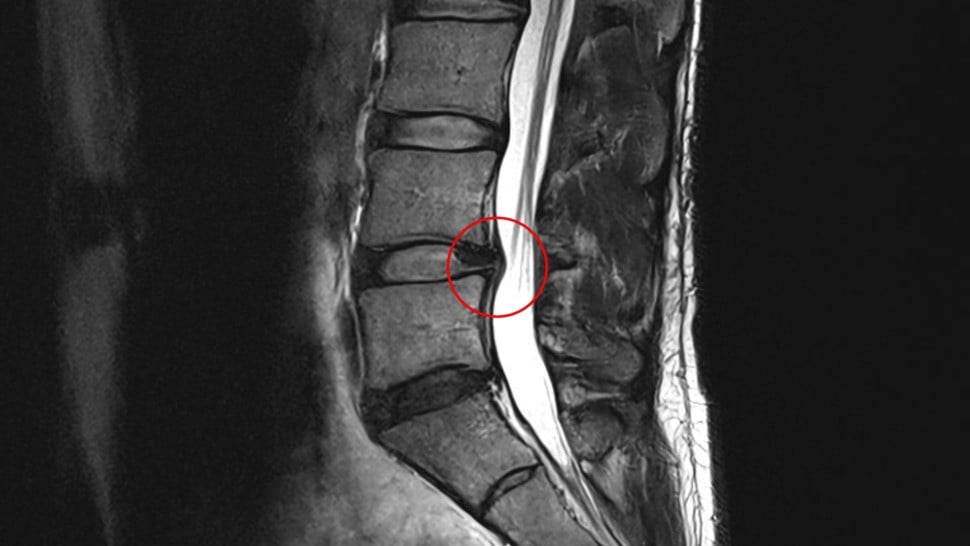

After a flurry of confused denial laced with pain, I learned almost two months later via an MRI that I have a lumbar disc protrusion (L4/L5 for the spinal column nerds out there). Years of bad posture and a lack of proper core muscle training means that this little bit of disc is poking the nerves in my lower spinal canal sending errant pain signals to my brain. The doctors and physical therapists make it clear to me: I need to change my life - and my work life - to heal so that I can live pain-free in the future.